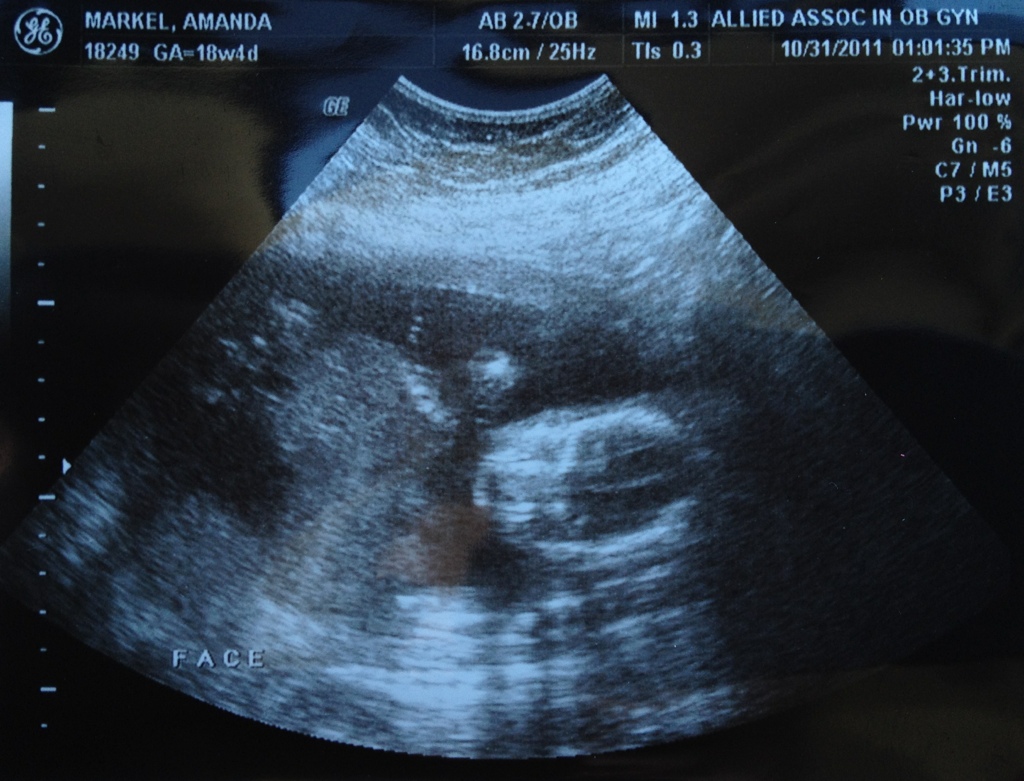

Meet Rebekah Oct31 by Ryan Markel (Name possibly subject to change.) The delicate balance of the Markel will be upset in a few months, and now we know that it will be on the side of the girls. Share: Email a link to a friend (Opens in new window) Email Share on X (Opens in new window) X Share on Facebook (Opens in new window) Facebook Share on Tumblr (Opens in new window) Tumblr Share on Pinterest (Opens in new window) Pinterest Share on Posterous (Opens in new window) Posterous Share on Reddit (Opens in new window) Reddit Share on Hacker News (Opens in new window) Hacker News Share on Instapaper (Opens in new window) Instapaper Like Loading... Related